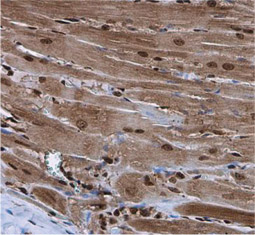

Cardiomyocytes make up the striated heart muscle. Unlike skeletal muscle cells, cardiomyocytes have a branching morphology.

Cardiac Troponin I antibody [N1C3] GTX109331

Cardiac Troponin I antibody (GTX109331)